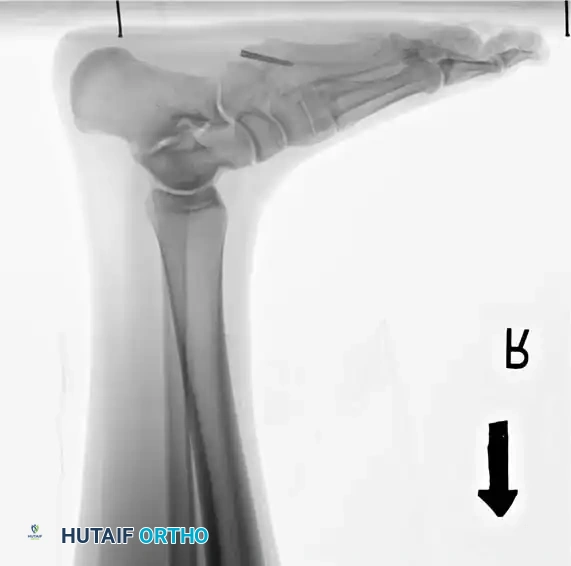

5. Drilling: Drive a 3.2-mm drill bit into the medullary canal. Confirm its intraosseous location using multi-planar fluoroscopy (anteroposterior and lateral radiographs).

7. Measurement: Estimate the required length of the screw from the intraoperative radiographs. The screw threads must bypass the fracture site and engage the dense diaphyseal bone distal to the fracture.

Fig. 86-46 Internal fixation of fifth metatarsal fracture. A and B, Position of the drill bit confirmed with AP and lateral radiographs. C, A 6.5-mm malleolar screw and small iliac cancellous bone graft were utilized due to cortical hypertrophy and a history of repeated fractures. D, Several months post-union, the screw was removed at the patient’s request, though it may remain in place indefinitely.